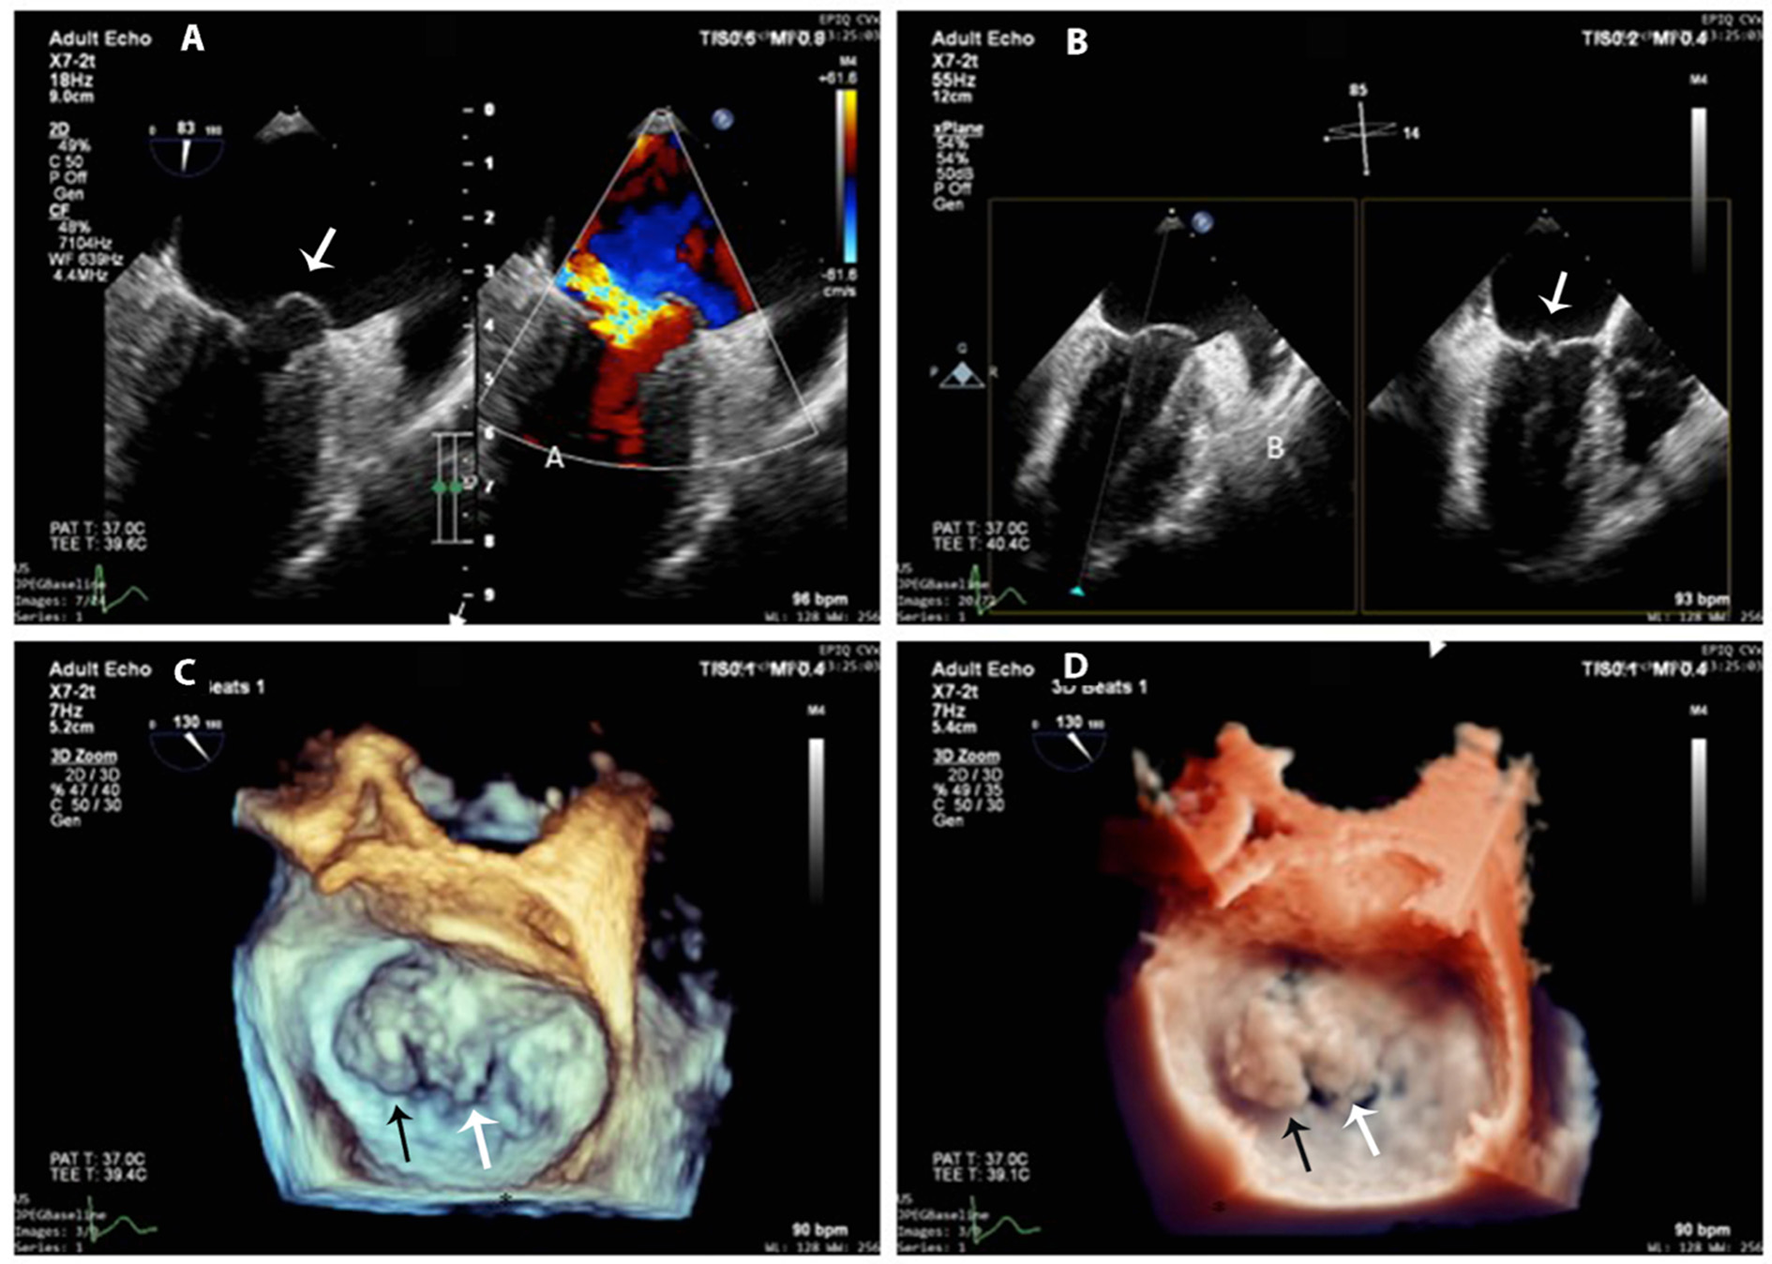

After the cardiac cystectomy, the eosinophilic count decreased significantly (13.1% at 4 days post-operation). Post-operative TTE showed an LV cavity devoid of masses, normal LV systolic function, and trivial mitral regurgitation. The patient continued receiving albendazole 200 mg b.i.d for 2 more weeks. Post-operative 12-lead and 24-h ambulatory ECGs were normal. At 1, 6, and 12 months after cardiac surgery, the patient felt well-without symptoms, and her blood tests, abdominal ultrasound, and echocardiographic LV and RV systolic functions were normal. However, the 12-month 2D-TTE revealed mild to moderate mitral regurgitation due to prolapsed A1 and A2 segments that were confirmed by 3D transesophageal echocardiography (3D-TEE) (Figures 4A–D); the prolapse was probably due to resection of the anterior papillary muscle at the time of cyst removal. The 3D-TTE and 3D-TEE showed no abnormal structures in the LV cavity, and the LV dimensions and ejection fraction were within normal limits and without any significant changes from the previous echo studies.

Figure 4

3D-TEE at 1-year follow-up. (A) Mitral anterior leaflet prolapse (white arrow) on a mid-esophageal two-chamber view (left panel) and the origin of the regurgitation jet with color Doppler (right panel). (B) X-plane imaging with two orthogonal views shows exactly the prolapsed scallops (white arrow). (C,D) 3D-zoom images of the mitral valve from the left atrial perspective (surgeon's en-face view) show exactly A1 (black arrow) and A2 (white arrow) prolapse (C) normal 3D gain vs. (D) true view mode.